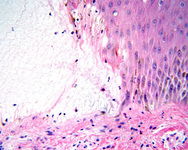

Буллезный пемфигоид

В полости пузыря имеются фибрин и эозинофилы

Из коллекции д-ра Весны Петрон-Росик (Dr Vesna Petronic-Rosic)